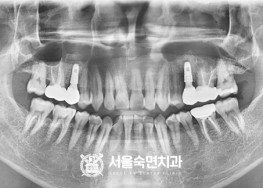

임플란트-치료-전후사진

서울대학교-출신-보건복지부-인증-통합치의학과-전문의-2인-책임관리